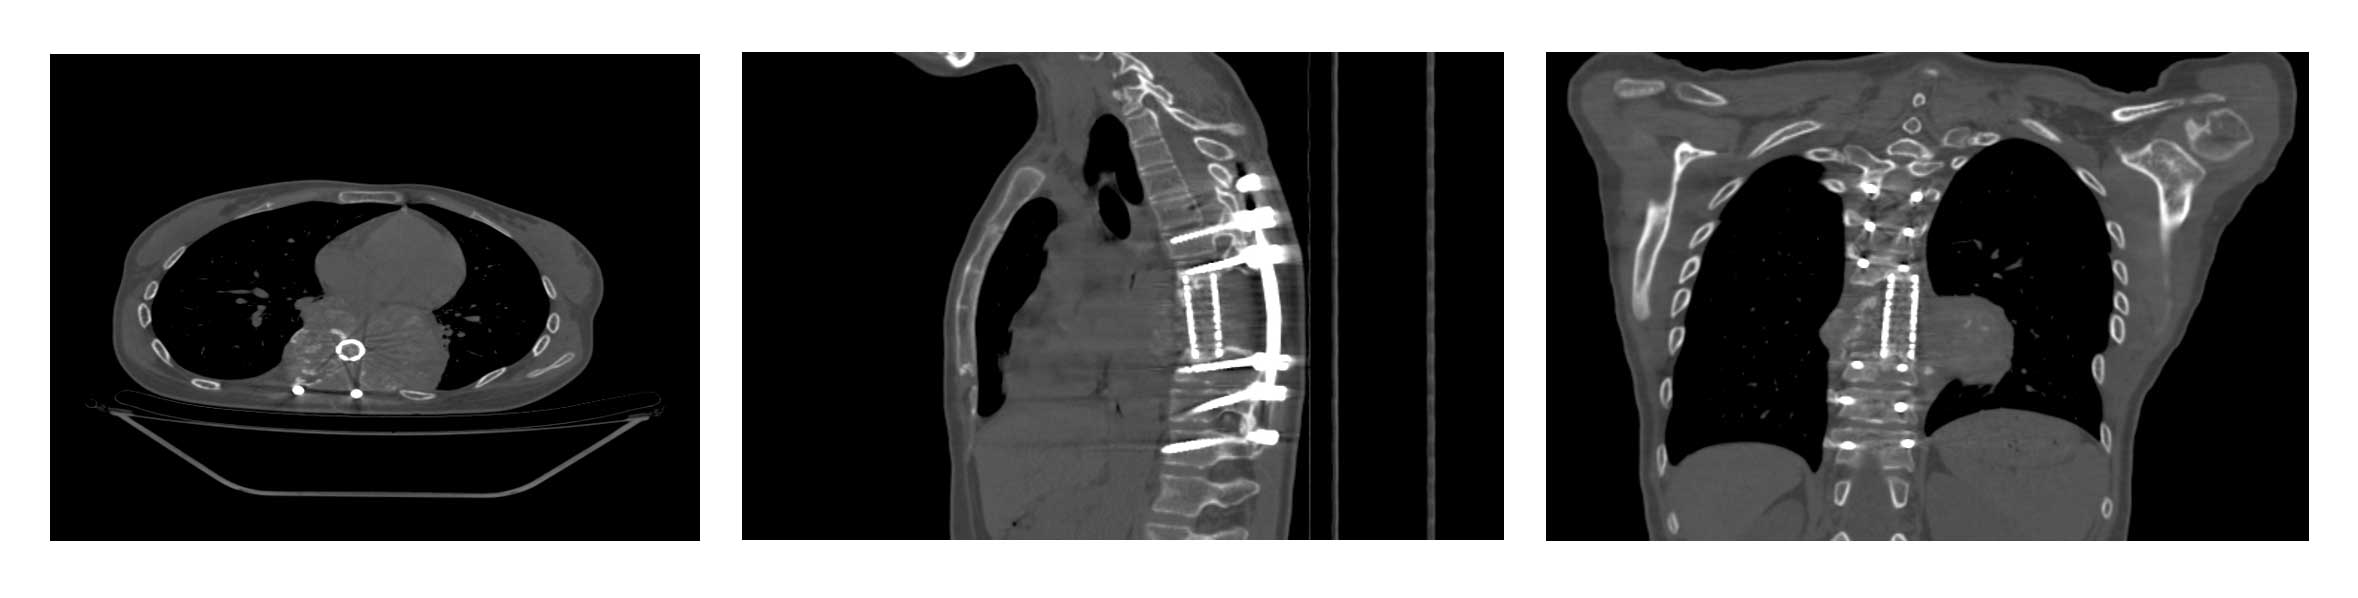

Ameliyat Öncesi: Tomografi kesitlerinde daha önce uygulanan kafes ve enstrümentasyon ile birlikte tümör nüksü görülmekte.